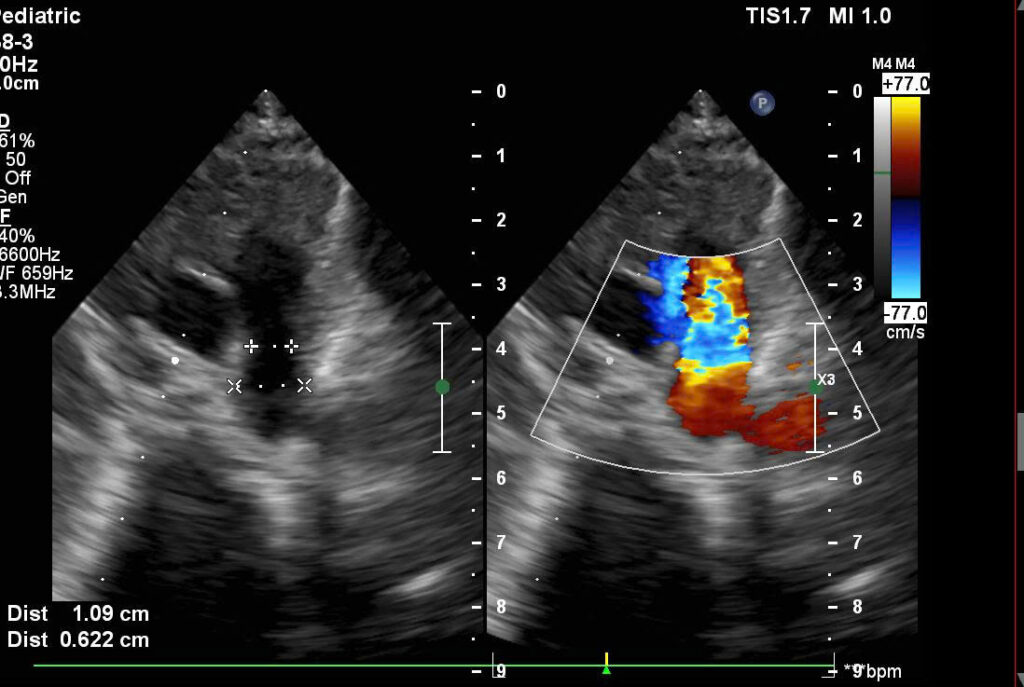

Từ các kết quả cận lâm sàng và Siêu âm Doppler tim, van tim cho thấy trẻ còn ống động mạch lớn đường kính phía phổi 4.6mm, đường kính phía chủ 9.1mm, hở van ba lá trung bình, Pgmax qua van ba lá 57mmhg; điện tim thường: nhịp xoang tần số 128 chu kỳ/phút; Các bác sĩ đã hổi chẩn chuyên khoa và chỉ định phẫu thuật bệnh tim bẩm sinh đóng ống động mạch, phương pháp Gây mê nội khí quản.